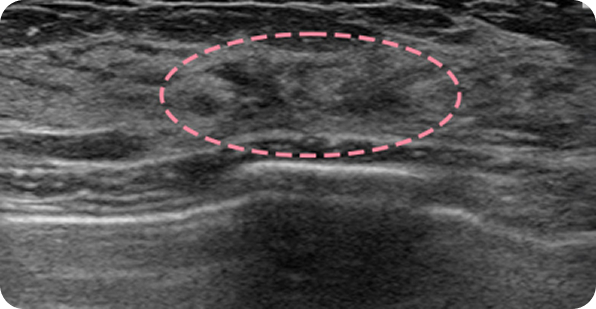

유방 섬유선종은 20~30대 젊은 여성에게 흔히 발생하는 양성 종양 으로, 대체로 위험성이 크지 않습니다. 하지만 드물게 악성으로 진행하는 경우가 있고 환자분께서 가족력으로 인한 불안을 느끼셔서 이번 사례에서는 예방적 차원에서 제거를 시행했습니다. 수술은 어렵지 않게 진행되었고, 1년 후 검사에서도 반흔 외에 재발 없이 깨끗한 결과를 확인할 수 있었습니다.